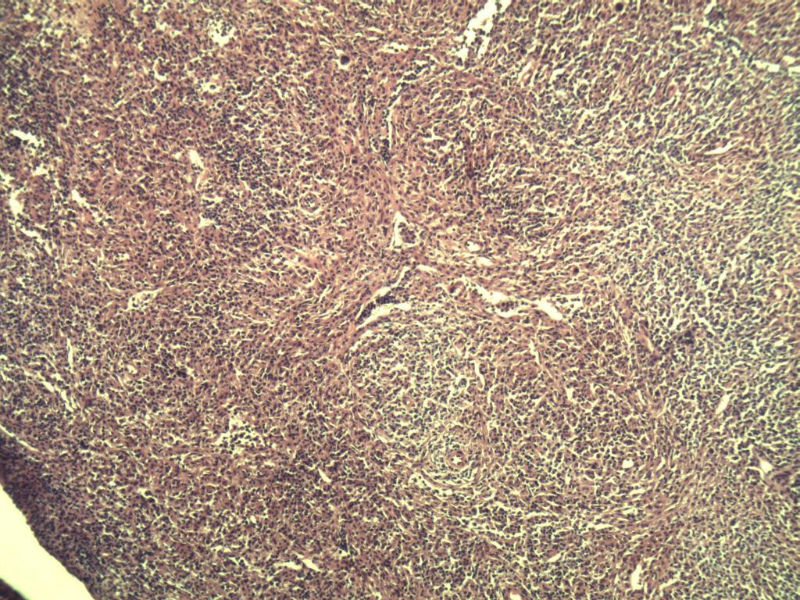

男,38岁,腹股沟 多枚淋巴结活检  直径 0.2-0.5 请各位老师看看 是什么 谢谢了!

"畏寒,发热咳嗽1年,加重伴腹部疼痛2月" 2月前患者感腹部疼痛不适伴大便呈稀大便,量不详,伴腰骶部疼痛,胸片:纵膈及右肺门多发性淋巴结肿大,进一步完善胸部CT:右肺及中叶病变,纵膈及肺门多发淋巴结肿大,结核性可能,脾脏增大,PPD(-),1个月来患者出现中上腹食欲不振,体重进行性消瘦,全身疲乏无力,3天前到医学院就诊,腹部B超:右肝囊肿,胆囊壁毛糙,脾大,胰周多个减弱回声,淋巴结不能除外,腹水,血常规示:WBC16.36x109 /L,N%14.25%,RBC2.63x1012/L ,HGB 66g/L 。右侧腋窝及腹股沟可扪及多枚淋巴结,压痛,无明显粘连。

名称:图3

副皮质区增生,纤维化显著,细胞呈多形性,有一些多核巨细胞及一些异型细胞,病理性核分裂易见,胞浆红染,散在的小淋巴细胞,T细胞淋巴瘤不能除外,树突细胞肉瘤等鉴别。免疫标记。CD21、CD3、CD5、CD10、CD20、CD79a、PD1、CD68、CXCL13、KI-67、CD68、CD163等,据切片选择。不知对否。

淋巴结正常结构破坏,可见大的异型细胞,上皮样或梭形,恶性肿瘤,依据病史,首先考虑淋巴造血系统疾病,大中小细胞混杂,大细胞多,形态多样,可见多核瘤细胞,除以上考虑外需鉴别间变大、组织细胞肉瘤、指状突/树突细胞肿瘤、HL等,还需排除肉瘤或癌转移,尽管病人年轻,加上ALK、CK、S-100、CD1a。